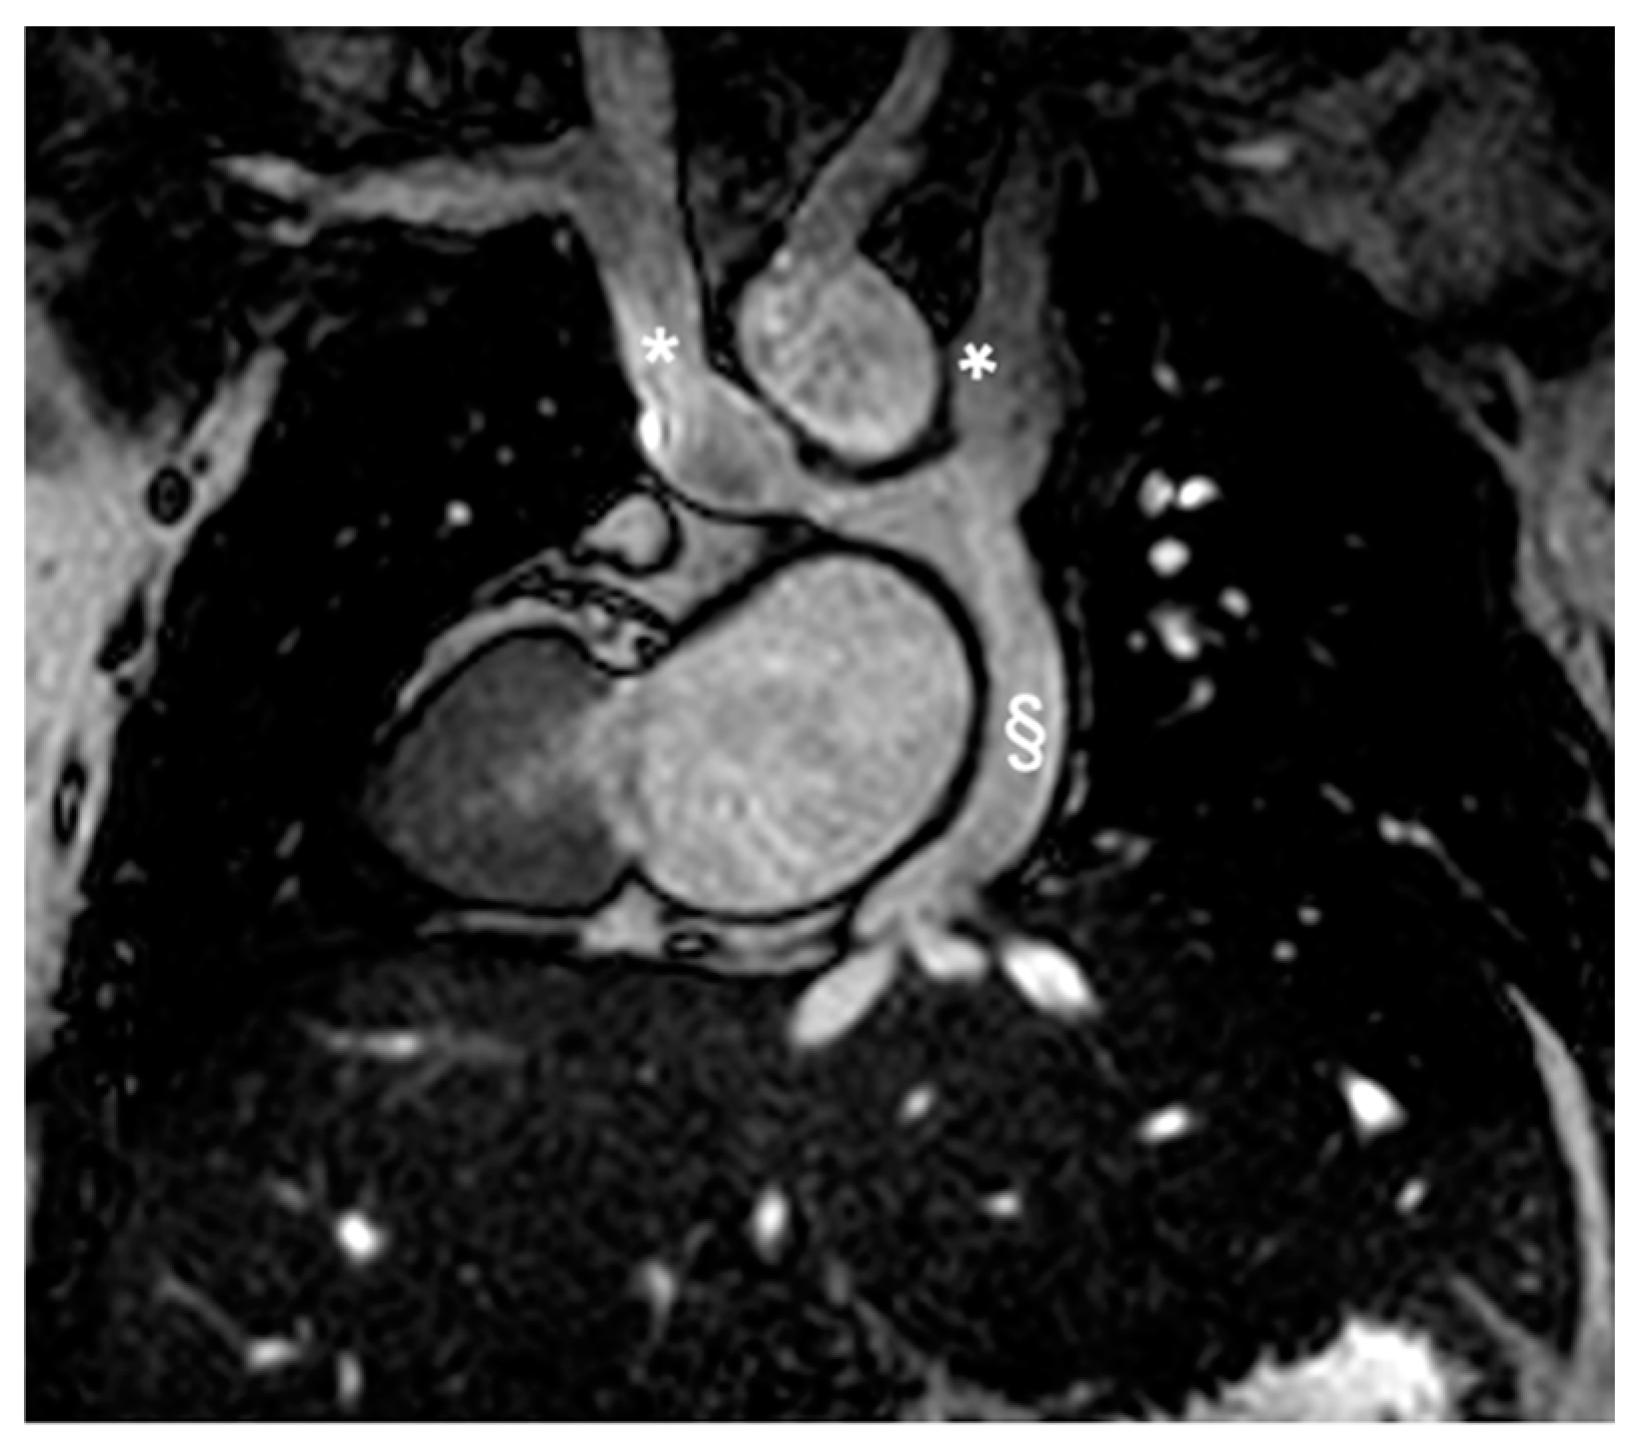

Figure 2.

Cine bSSFP image of D-TGA post-atrial switch operation using the Senning technique. The image shows the pulmonary veins (*) being redirected through the baffle into the right atrium and then to the subaortic positioned sRV.

Figure 3.

Cine bSSFP image of D-TGA following an atrial switch operation using the Senning technique. This image illustrates the pathway of the systemic veins, with the superior vena cava (*) and the inferior vena cava (§) shown.